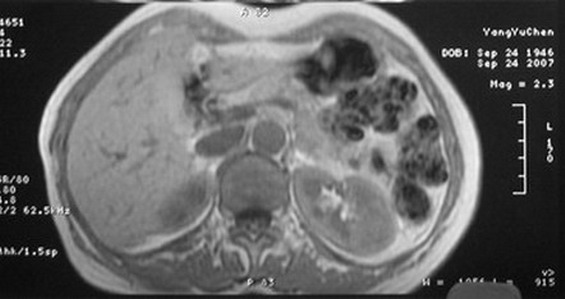

标题: MRI2066:腹膜后占位,请会诊,CT18531近期扫描图像

无明显不适,体检发现,

mri基本排除血管类肿瘤,明显强化说明极富血供,临床无症状,考虑胰岛细胞瘤可能大。

强化明显,并见有血管与之相连;考虑巨淋巴增生症.

极富血供的占位性病变,首先考虑良性,期待结果。